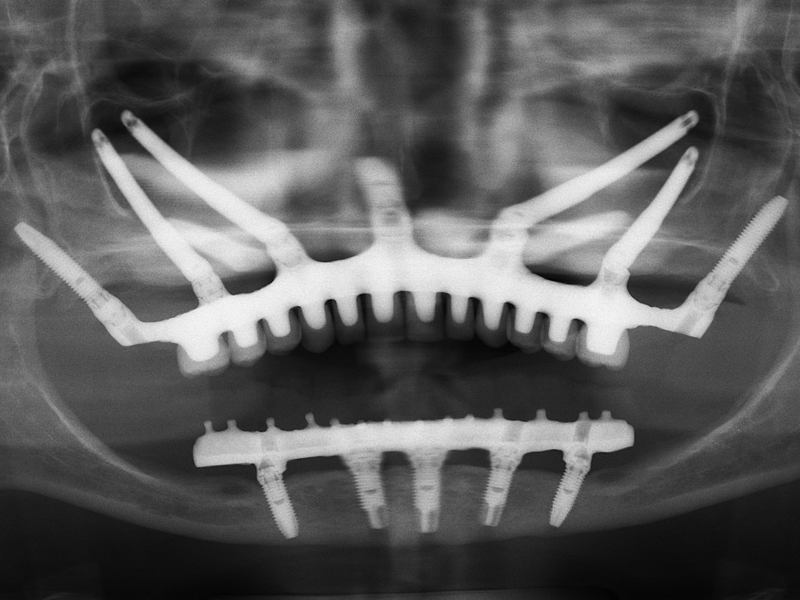

Zygomatic implants

The zygomatic implants are an excellent solution in cases of patients with little jaw bone. In this type of intervention the advantage is to be able to insert an implant without additions or regeneration of jaw bone.

Zygomatic implants can be considered aneffective alternative to bone grafting. They allow the patient to undergo the removal of any autologous bone material and therefore also to the stitches and a longer wait to have a fixed prosthesis.